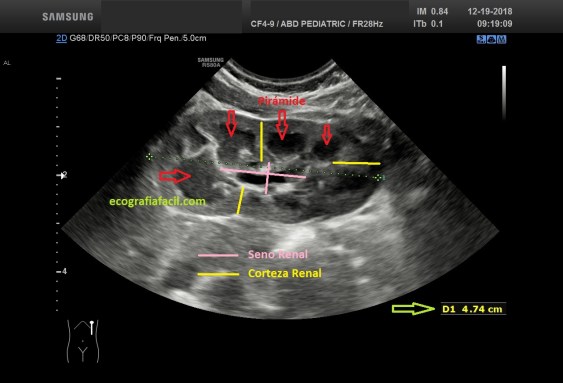

El Riñón ecográficamente normal es este:

En la imagen superior puedes ver un Riñón donde Corteza y Seno Renal están claramente diferenciados, se observa los Pielones Caliciales…

We started this series of micro posts where we will review the usual pathology that can be found in pediatric abdominal ultrasound exploration, yes I know, this blog is not pathology, but I think it is interesting to teach the pathology and its semiology in the minimum possible expression, and above all, the comparison with normality, which for a Radiology Technician is the basis. We begin with the Hydronephrosis, and its degrees, knowing this disease will help us to recognize its signs, and above all, stop where it talks about the degrees of hydronephrosis, superinteresting. In some antenatal ultrasound and gynecologxs are already able to detect this condition that then have to confirm in the neonatal stage. The kidney, which is ecographically normal, is this: